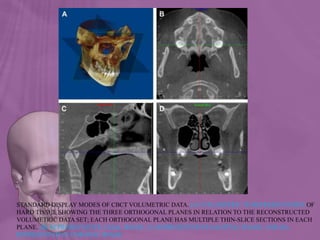

IMAGE DISPLAY

• The availability of CBCT technology provides the dental

STANDARD DISPLAY MODES OF CBCT VOLUMETRIC DATA. (A) VOLUMETRIC 3D REPRESENTATION OF

HARD TISSUE SHOWING THE THREE ORTHOGONAL PLANES IN RELATION TO THE RECONSTRUCTED

VOLUMETRIC DATA SET; EACH ORTHOGONAL PLANE HAS MULTIPLE THIN-SLICE SECTIONS IN EACH

PLANE. (B) REPRESENTATIVE AXIAL IMAGE. (C) REPRESENTATIVE SAGITTAL IMAGE, AND (D)

REPRESENTATIVE CORONAL IMAGE

• 151.

STANDARD DISPLAY MODESOF CBCT VOLUMETRIC DATA. (A) VOLUMETRIC 3D REPRESENTATION OF HARD TISSUE SHOWING THE THREE ORTHOGONAL PLANES IN RELATION TO THE RECONSTRUCTED VOLUMETRIC DATA SET; EACH ORTHOGONAL PLANE HAS MULTIPLE THIN-SLICE SECTIONS IN EACH PLANE. (B) REPRESENTATIVE AXIAL IMAGE. (C) REPRESENTATIVE SAGITTAL IMAGE, AND (D) REPRESENTATIVE CORONAL IMAGE